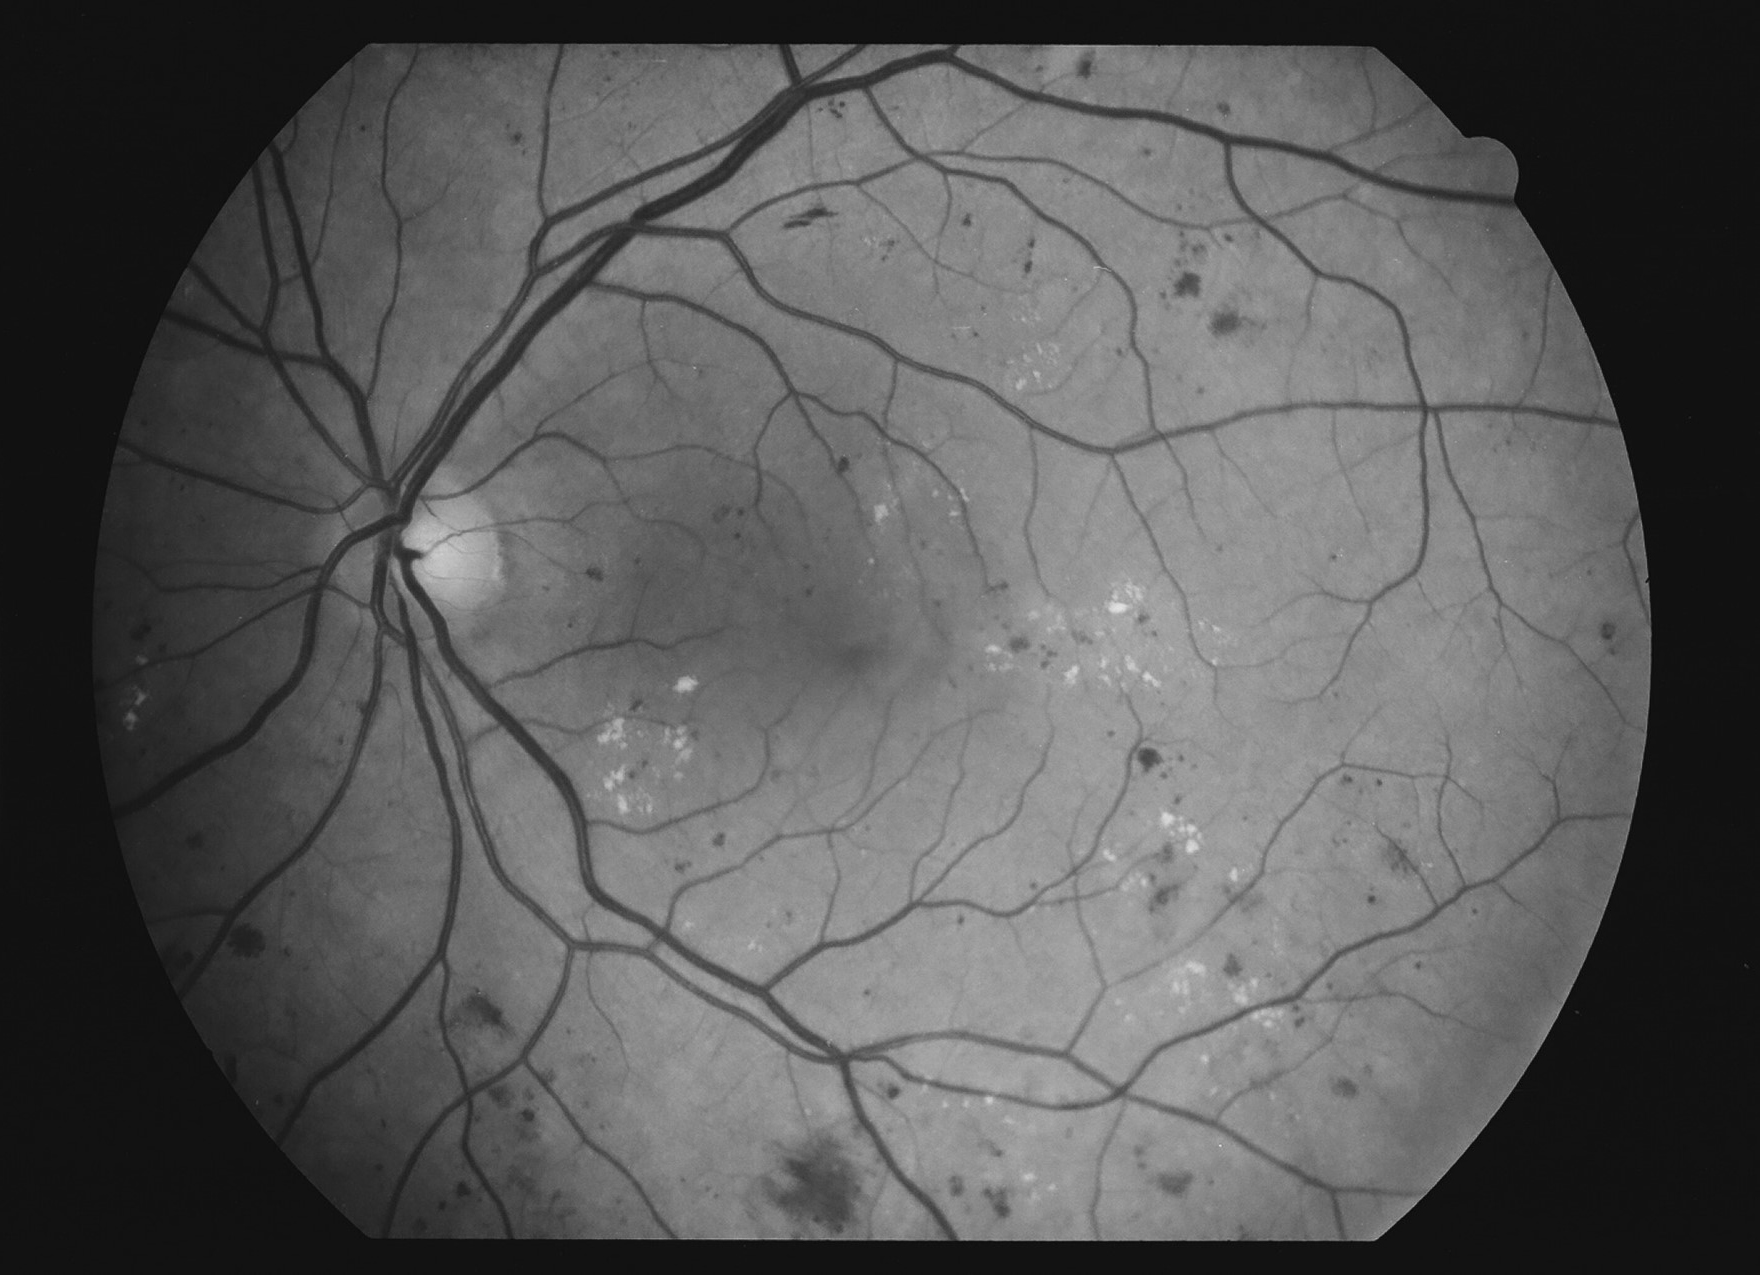

Kuva 10.

Diabetes, proliferatiivinen retinopatia, makulaturvotus, oikea silmä. Mikroaneurysmia, mikroinfarkteja, vuotoja, lipidieksudaatteja, IRMA:a ja uudissuonia.

Kuva 11.

Diabetes, proliferatiivinen retinopatia, makulaturvotus, vasen silmä. Mikroaneurysmia, mikroinfarkteja, vuotoja, lipidieksudaatteja, IRMA:a ja uudissuonia.